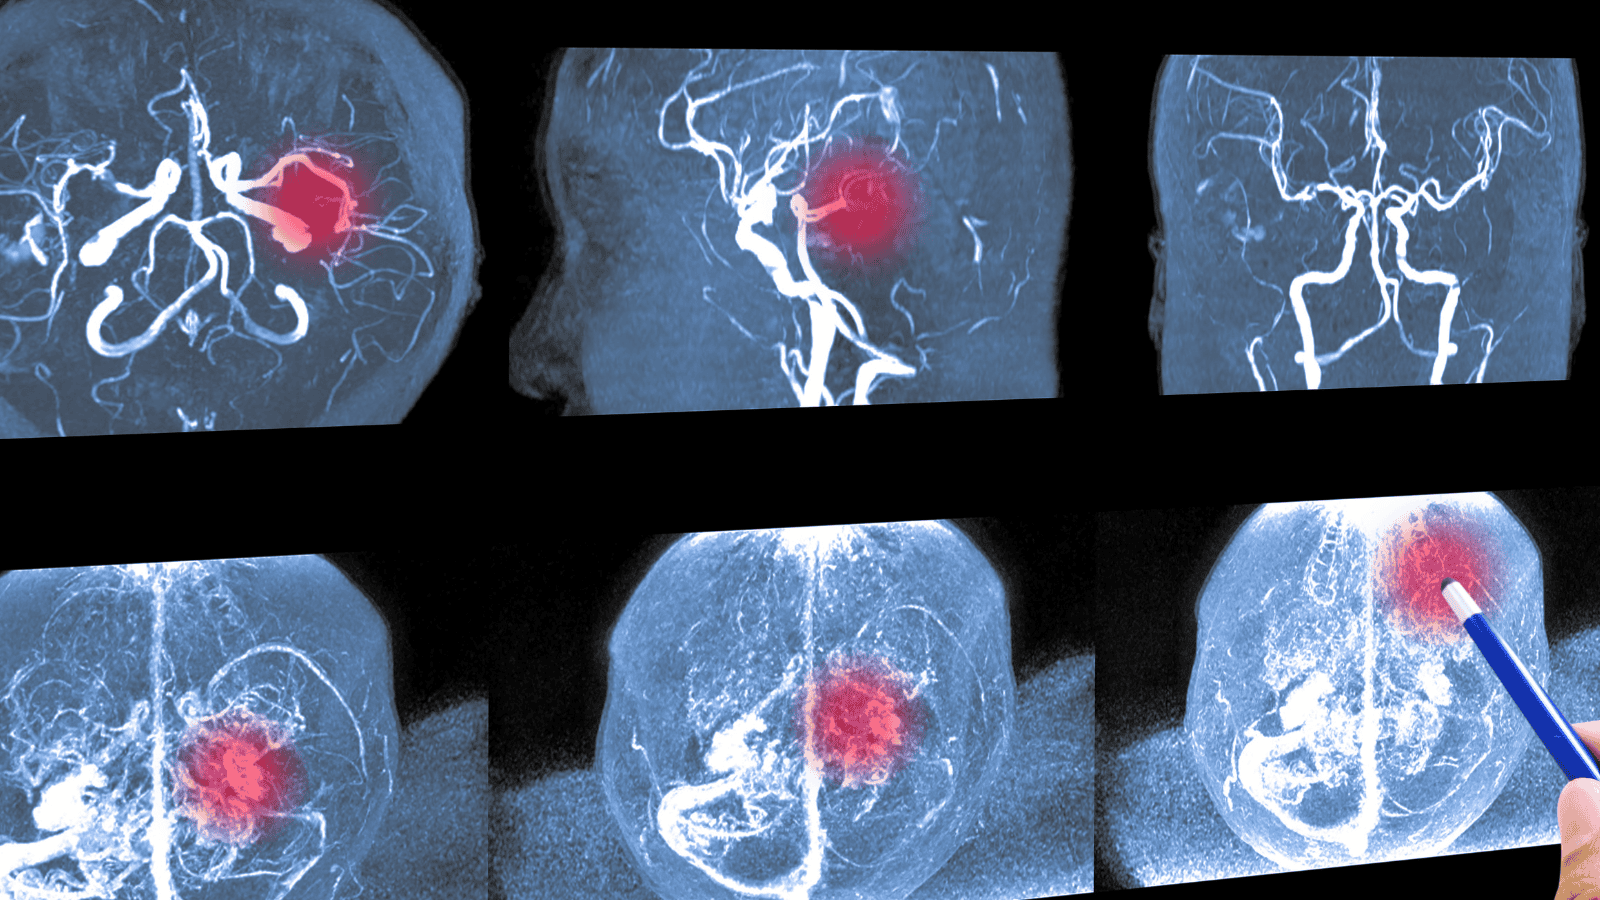

Takie objawy wysyła tętniak przed pęknięciem. Chorzy wypowiadają te "magiczne słowa"

fot. Tonpor Kasa/Getty Images

Tętniak mózgu to patologiczne poszerzenie naczynia krwionośnego w mózgu, które wynika z osłabienia jego ściany. Proces jego powstawania może mieć charakter wrodzony lub nabyty. Do przyczyn nabytych zalicza się między innymi miażdżycę, nadciśnienie tętnicze oraz stany zapalne ścian naczyń. Zmiana ta może rozwijać się latami, nie dając przy tym żadnych sygnałów ostrzegawczych.

Statystyki dotyczące częstości występowania tego schorzenia są zróżnicowane, a szacunki wskazują, że dotyczy ono od 0,2 do 7,9% populacji. Aż 88% tętniaków skutkuje krwotokiem podpajęczynówkowym, natomiast 8% daje objawy przypominające guza mózgu. Jednocześnie około 4% zmian wykrywa się zupełnie przypadkowo.

Tętniaki rozwijają się zwykle powoli i są często diagnozowane dopiero u osób powyżej 40. roku życia. Większość z nich ujawnia się dopiero w momencie pęknięcia, co w jednej chwili może doprowadzić do dramatycznego krwotoku. Takie zdarzenie stanowi bezpośrednie zagrożenie i może prowadzić do śmierci.